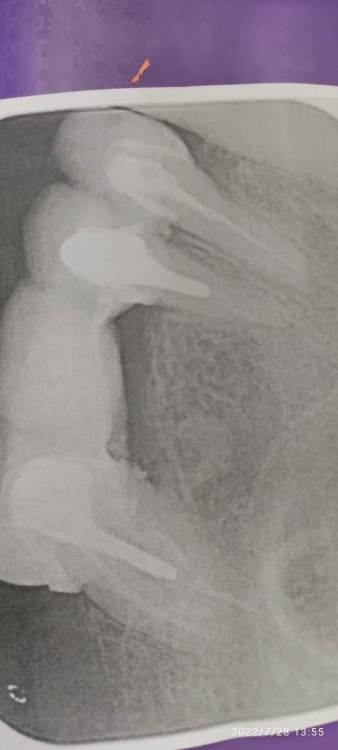

Добрый день ,4 месяца распирает зуб  под 1 коронкой,не болит но постоянно чувствую. Сменили коронку на новую но ничего не поменялось . Посмотрите пожалуйста снимок, в чем проблема. Неделю назад таким образом, сама нашла и врач (другой) исправили давление моста на десну..

IMG_20220728_135500.jpg